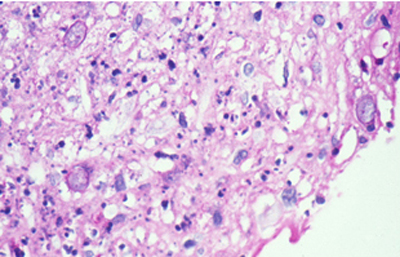

Cuando el examen patológico se realiza en cortes de tejido corneal procesados en parafina, (biopsias y discos de córnea de queratoplastias) las coloraciones que empleamos usualmente son la coloración de Hematoxilina-Eosina (Figura 49), el Blanco de Calcofluor. (Figura 50), la de PAS (Figura 51 y 52). De nuevo, la consideración de que una infección corneal puede ser causada por Acantamoebas es la condición indispensable en el diagnóstico diferencial para llegar a su diagnóstico

Acanthamoeba H-E, Original x160

Fig. 49 H-E, Original x160